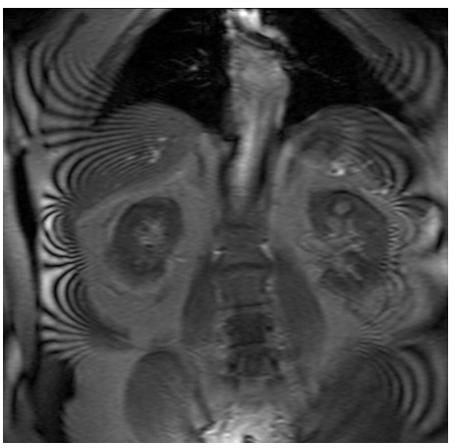

aliasing (ear lobe into middle of image)